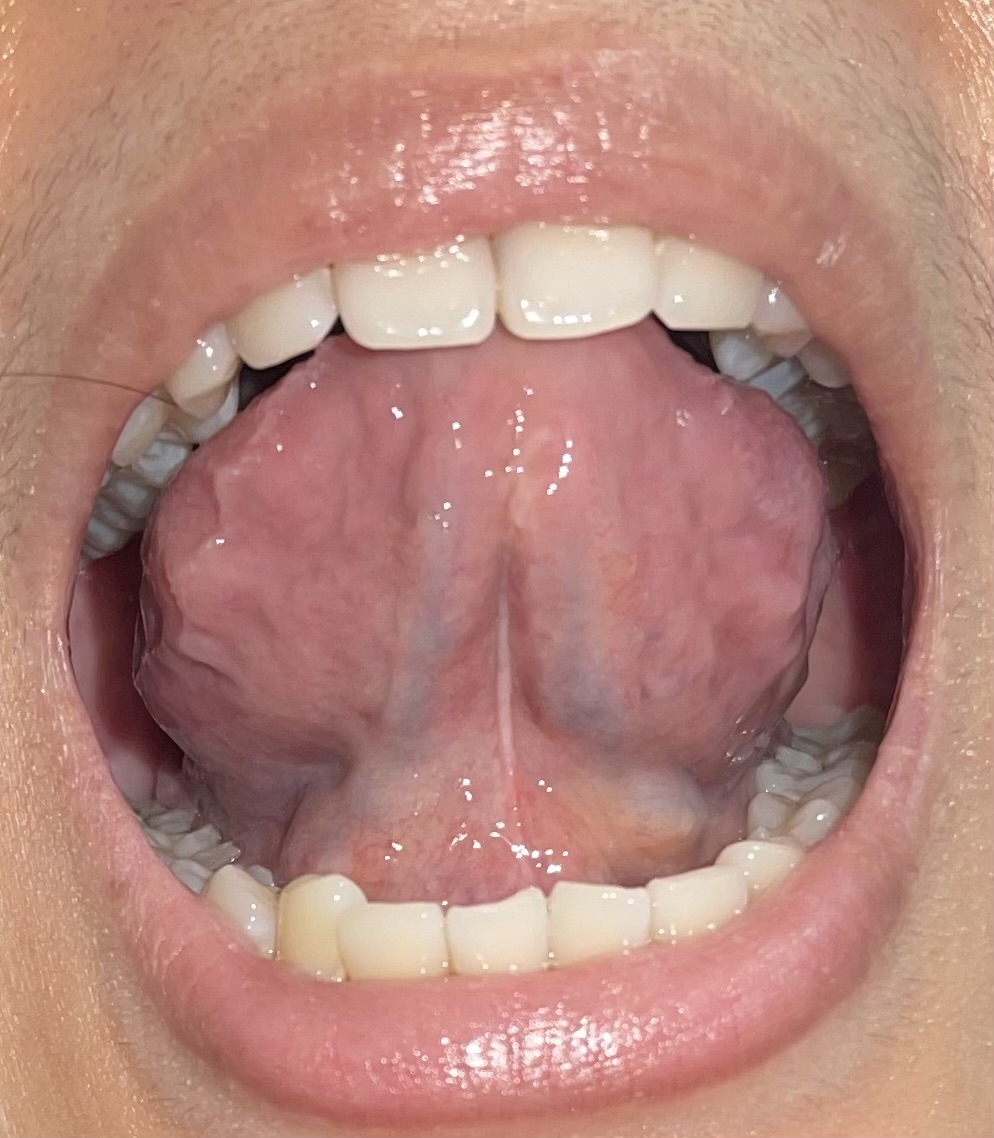

9 เมษายน 2568 17:43:25 #1 https://haamor.com/media/create_topic/20250409174126.jpeg https://haamor.com/media/create_topic/202504091741261.jpeg https://haamor.com/media/create_topic/202504091741262.jpeg https://haamor.com/media/create_topic/202504091741263.jpeg

เป็นติ่งแบบนี้ และมีตุ่มตรงกลาง เป็นอะไรไหมคะ กลัวเป็นหูดหงอนไก่ |

13 เมษายน 2568 10:50:02 #2 จากรูป ไม่ใช่หดูหงอนไก่ครับ ไม่ต้องทำอะไรถ้าไม่โตขึ้น |